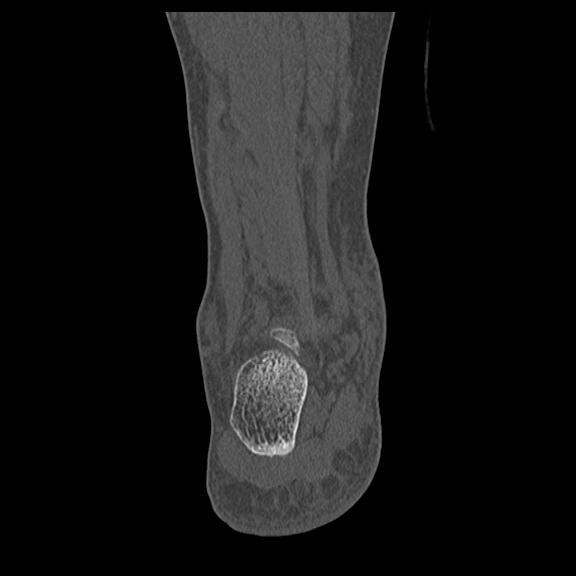

49554 3/13 膝 4R 3/16 4R 1/18 2R 78歳男性 膝蓋骨骨折